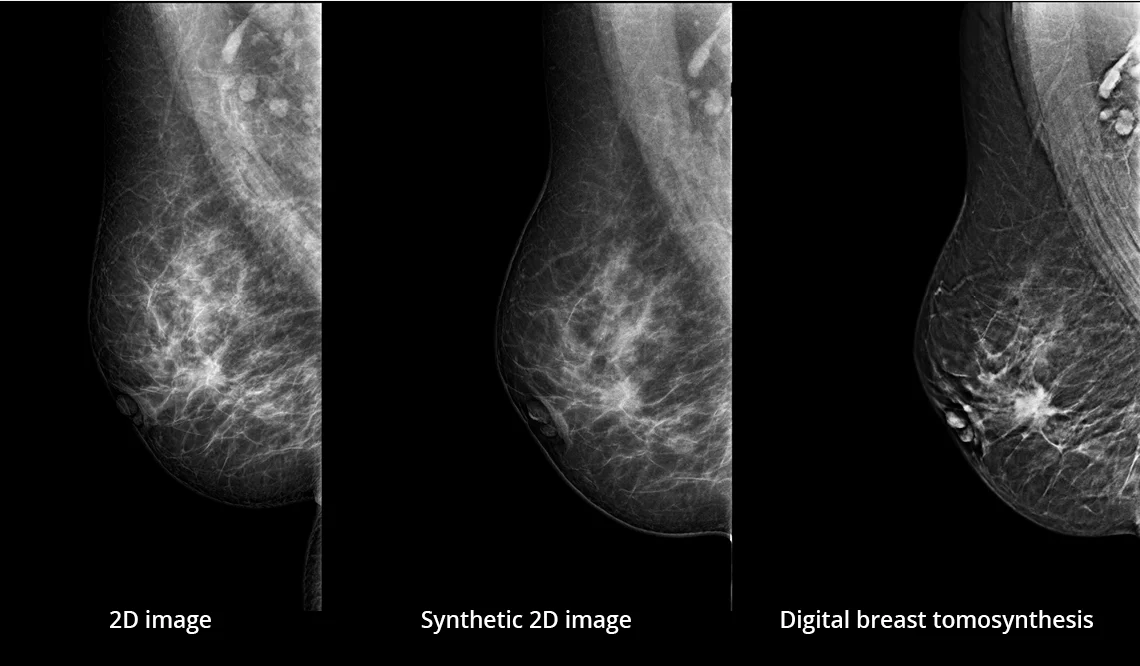

Zalety cyfrowej tomosyntezy piersi (DBT)

Cyfrowa tomosynteza piersi (DBT) tworzy warstwowy zestaw obrazów piersi, przez który można przewijać. Takie podejście eliminuje problem nakładających się struktur tkanek, co prowadzi do zwiększenia czułości i swoistości badania.

Unikalna metoda obrazowania Continuous Sync-and-Shoot™ firmy Planmed umożliwia uzyskanie obrazów tomosyntezy pozbawionych rozmycia ruchowego. Dzięki temu obrazy są wyjątkowo wyraźne i zapewniają doskonałą widoczność mikrozwapnień oraz innych drobnych struktur tkankowych.

Obrazy Kliniczne Planmed Clarity 3D